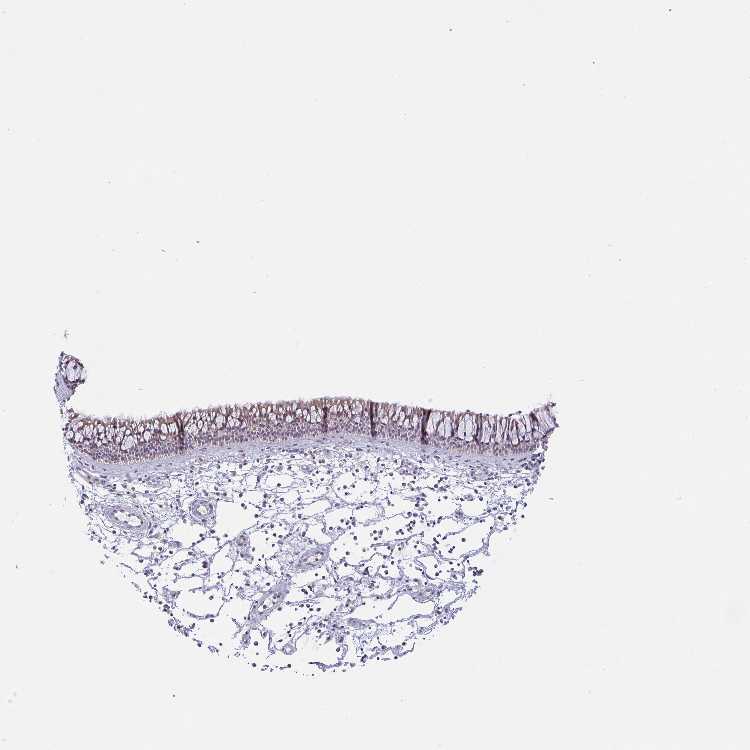

TISSUE PRIMARY DATA NASOPHARYNX Show tissue menu

NASOPHARYNX - Antibody stainingi

Antibody staining in the annotated cell types in the current human tissue is reported as not detected, low, medium, or high, based on conventional immunohistochemistry profiling in selected tissues. This score is based on the combination of the staining intensity and fraction of stained cells.

Each image is clickable and will lead to virtual microscopy that enables deeper exploration of all samples and also displays staining intensity scores, fraction scores and subcellular localization as well as patient and tissue information for each sample.

Antibody HPA054829

Respiratory epithelial cells Low